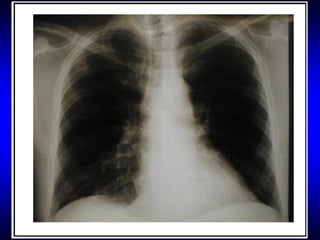

 Edema pulmonar, com estertores e sibilos

REPERCUSÕES SISTÊMICAS DO CHOQUE

 Pulmão

Edema pulmonar não cardiogênico

Lesão pulmonar aguda

SARA